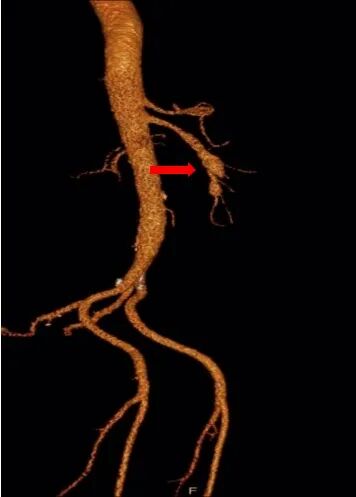

术前查腹腔动脉CTA示:肠系膜上动脉夹层伴动脉瘤。

患者肠系膜上动脉夹层动脉瘤,真腔明显缩小,假腔增大,有胃肠道缺血表现,有手术指征,未见手术禁忌。

术前造影图像

患者取仰卧位,双侧腹股沟区消毒铺单后局麻下分别经双侧股动脉穿刺置入7F(右侧)/5F(左侧)血管鞘组,予40mg肝素钠静脉注射全身肝素化,先经左股动脉插入4FRH导管,将导管头端置于肠系膜上动脉开口处,注入对比剂行肠系膜上动脉IADSA;再经右侧股动脉插入7F长鞘至肠系膜上动脉开口,旁路加压滴注生理盐水;明确病情后选取工作角度,先经4FRH导管路途下同轴送入1.7F栓塞微导管,旁路加压滴注生理盐水,经微导丝配合将其头端至于肠系膜上动脉夹层囊状动脉瘤腔内,于动脉瘤填入5枚弹簧圈行夹层动脉瘤弹簧圈填塞术;经右侧股动脉长鞘入路沿导丝送入1枚支架(SmartFlex 6mm×80mm,USA)该支架具有可预见的近端定位+参考Marker,准确定位后行肠系膜上动脉真腔成形术,支架覆盖夹层段。复行肠系膜上动脉IADSA示:支架位于肠系膜上动脉主干夹层段,支架覆盖夹层动脉瘤出入破口,支架内血流通畅,分支血管显影良好,支架以远血管主干及分支显影较术前增多增浓,多发夹层动脉瘤腔内弹簧圈均匀填塞。手术结束,使用Exoseal封堵止血系统闭合双侧股动脉穿刺点。